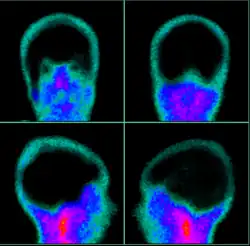

| Exame de cintilografia cerebral sem perfusão, corroborando o diagnóstico de morte encefálica (ME) | |

Cintilografia cerebral. Evidente ausência de perfusão da massa encefálic